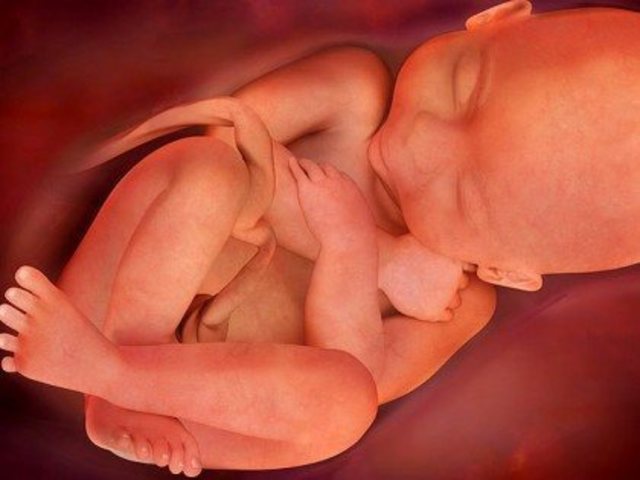

El cigoto se convierte en embrión. desarrolla el sistema circulatorio, el corazón y brotes de lo que posteriormente serán los brazos y piernas. presenta una cola que es el inicio del cordón umbilical. Se forman los dedos de las manos y pies, los labios, el hígado, orejas y ojos.

Las uñas empiezan a crecer y los huesos a endurecer, los riñones producen orina y los órganos sexuales empiezan a desarrollarse.

Comienza a crecer el cabello y los órganos sexuales interno se ubican en la posición de la cadera

Crece un bello fino en el cuerpo y una capa de grasa que ayudará a proteger la piel del bebé cuando nazca.

Aparecen pestañas y cejas.

Inicia cambios físicos, regula actividades y momentos de sueño, los parpados se abren y se forma la retina.

El vello o lanugo se cae, y en el sexo masculino los testículos inician el descenso al escroto.

El feto tiene mas grasa corporal, las pupilas se contraen al exponerse a la luz.